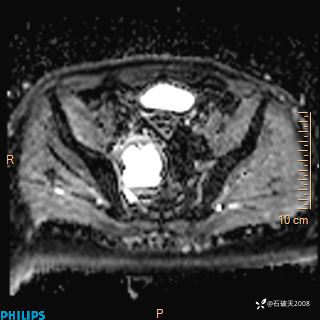

2023年3月份MRI影像

增强轴位